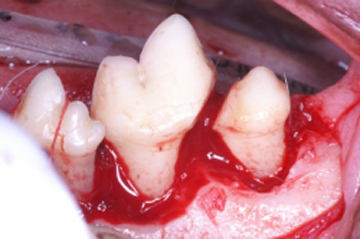

La periodontitis se clasifica como “Periodontitis leve” cuando el tejido óseo se ha destruido máximo en el tercio cervical; “Periodontitis moderada” cuando la destrucción ósea ha llegado al tercio medio de la raíz y “Periodontitis severa” cuando la destrucción ósea ha llegado al tercio apical de la raíz. La movilidad dental ligera aparece en la periodontitis moderada y la movilidad dental excesiva aparece en la periodontitis severa.

Haz CLICK sobre la imagen para ver descripción.